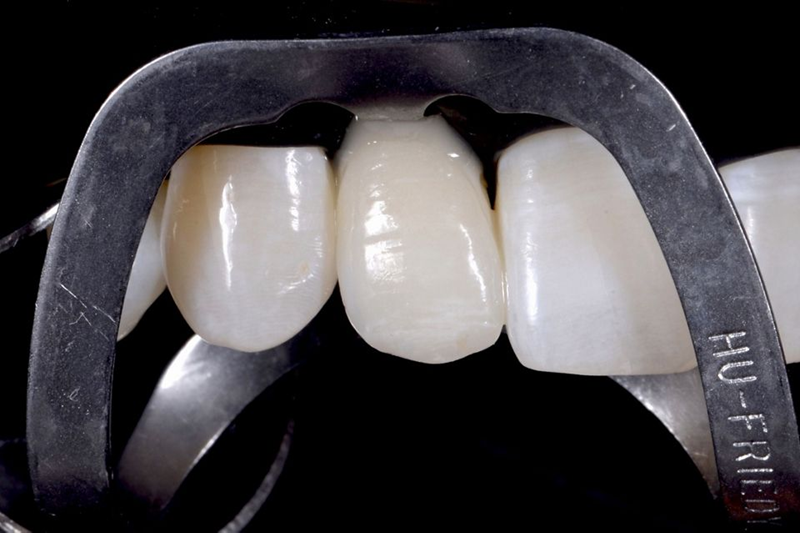

然后,对前庭侧陶瓷铣削后待贴面的氧化锆牙冠进行造型。一旦完成此步骤,就以此为参考生产氧化锆牙冠(图51)。铣削氧化锆牙冠和陶瓷贴面后,使用复合水泥将牙冠固定在 Variobase® 上(图 52)。然后,对最终的牙冠进行仔细抛光并调整以适应患者口腔中的位置(图53-54)。

Fig. 52: After the milling of the zirconia crown and its ceramic veneering, the crown was fixed on the Variobase® by...

Fig. 53: Vestibular view of the final crown.

Fig. 54: Palatal view of the final crown.